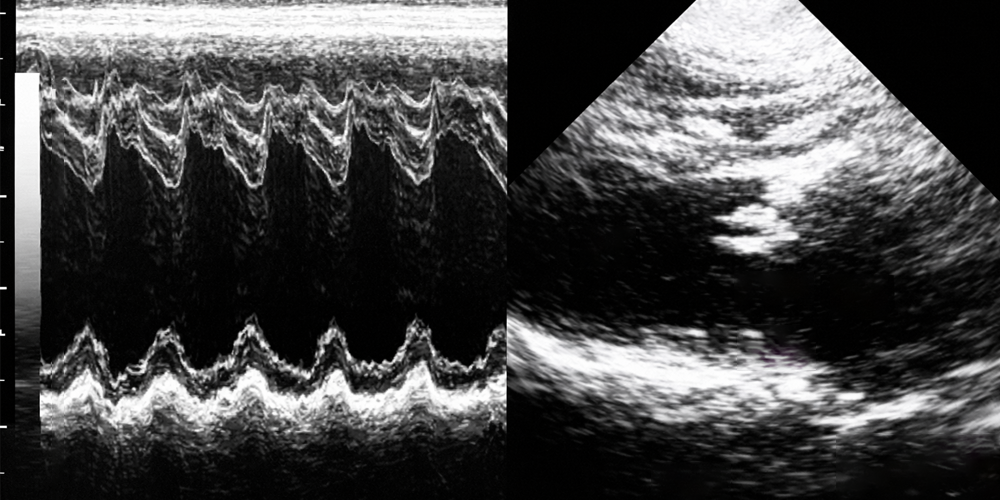

Sonraki gelişme real time ultrasonografi olmuştur. Yani, gerçek zamanlı ultrason. Bu tip ultrason siyah-beyaz-gri resimlerin tekrar tekrar çizilmesi ile bir çeşit canlı görüntü oluşturulması ile elde edilmiştir. Bugün muayenelerinizde en çok kullanılan yöntem budur.

İncelenen alanlarda sabit duran bölümlerle hareket eden bölümleri daha net ayırdedebilmek için, M-mod (Motion-modu) geliştirilmiştir. Kalp muayenesinde kullanılır.